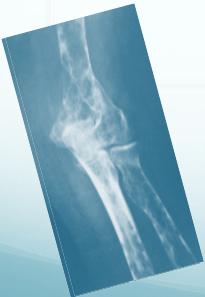

Bone Tumors and Tumor-like Conditions

Benign Bone Tumors

Malignant Bone Tumors